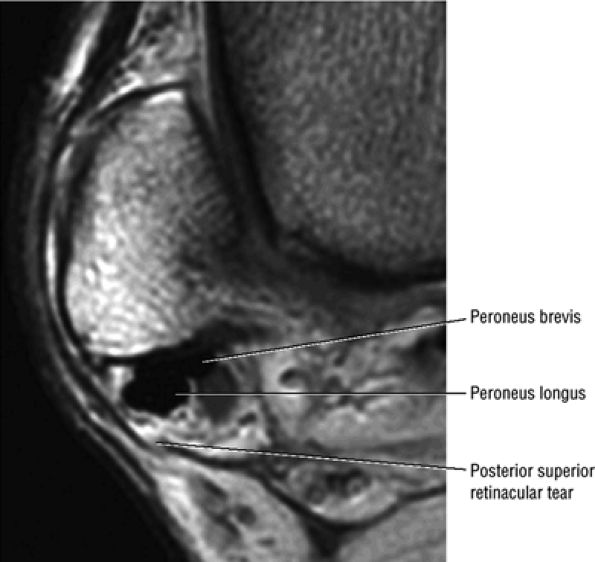

The peroneal retinaculum prevents the peroneal tendons from subluxing laterally over the lateral malleolus. Tears or stripping of the peroneal retinaculum from the lateral malleolus is inferred when subluxation or dislocation of the peroneal tendons is seen lateral to the lateral malleolus.